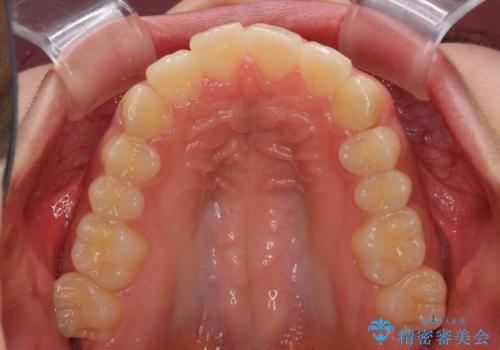

就職前にきれいな歯並びにしたい 大学生のインビザライン矯正

- 就職するまでに歯並びをきれいにしたいとのことで来院された患者様です。

前歯の叢生を気にしていましたが、極力突出感を改善できるようにすることとし、インビザラインにて矯正治療を行うこととしました。

改善の期待できない口元の突出感改善を希望されたため、いたずらに治療期間が延びましたが、きっちりと仕上がりました。